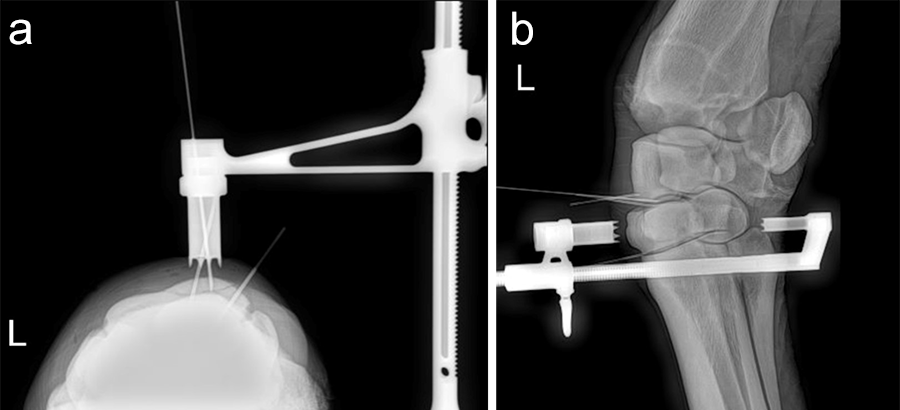

An articular fracture of the lateral wing of the distal phalanx was diagnosed at the track in this 3-year-old Standardbred racehorse, which was referred for surgery. Internal fixation was planned with a 5.5 mm cortex screw in lag fashion to restore and maintain articular congruency by fracture reduction and interfragmentary compression. Drill trajectory was planned with computed tomographic (CT) guidance with the horse awake and standing. Grids of barium paste dots were placed at proposed entry and projected exit sites. Once the ideal dot was selected from each grid the horse was anesthetized and the hoof prepared for surgery. The veterinary Screw Targeting Clamp (STC) was affixed to the hoof at the ideal dot in the entry and exit grids. Drilling, countersinking, measuring, tapping, and screw placement were achieved through the STC. The CT guidance and the STC allowed placement of the screw between the articular surface and vascular canal containing the terminal arterial arch, and in an orientation that resulted in accurate reduction instead of translation of the fracture fragment and parent bone.

A frontal plane fracture of the third carpal bone was diagnosed at the track in this 3-year-old Thoroughbred racehorse, which was referred for surgery. Internal fixation was planned with a 3.5 mm cortex screw in lag fashion. The Screw Targeting Clamp (STC) placement was guided using needles with radiographic and arthroscopic imaging. From skin incision to screw placement, lag screw fixation was achieved through the STC without movement or removal of the device.